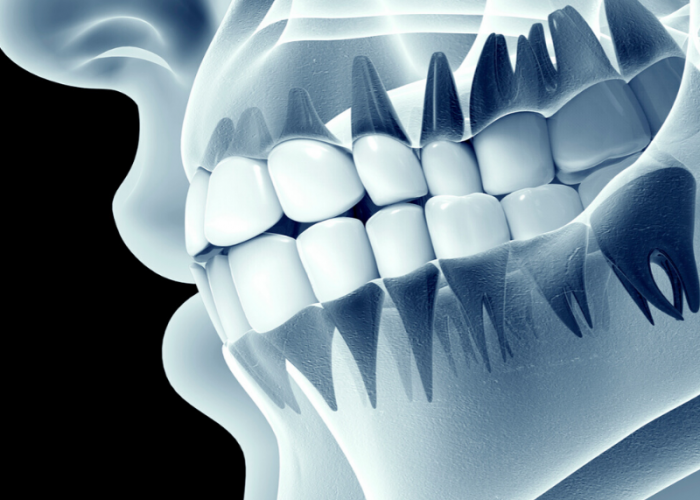

Dental X-Ray

High-resolution digital dental X-rays ensure precise detection of cavities, infections, and bone loss. Safe, quick, and effective, they help in early diagnosis for better treatment outcomes.